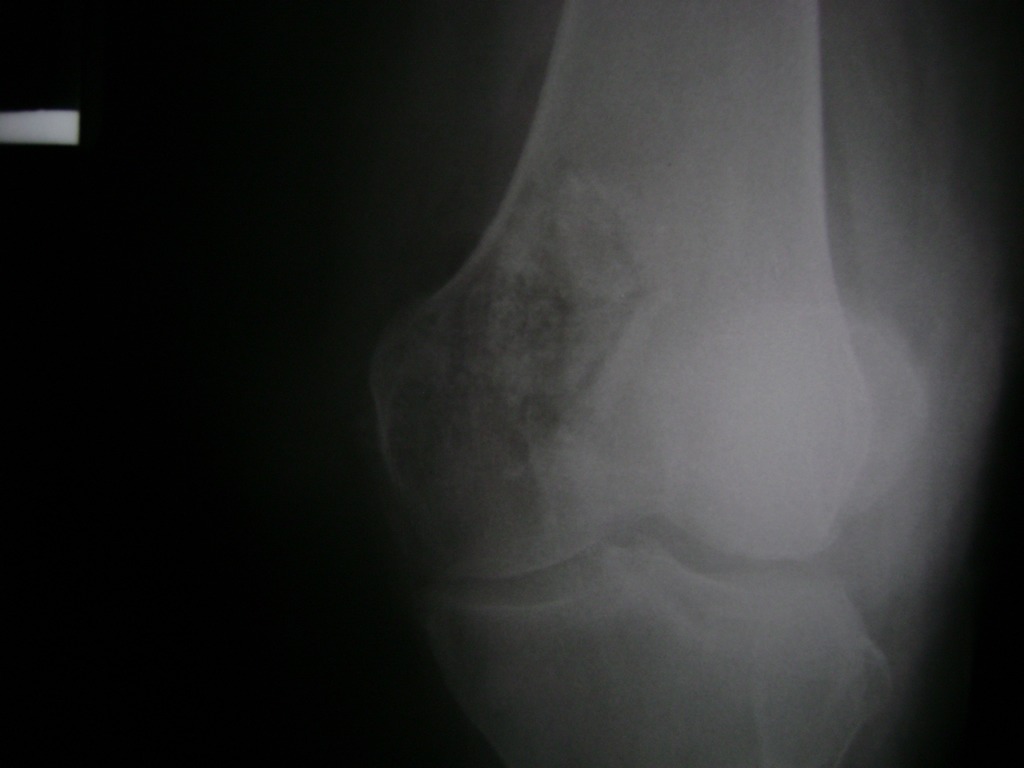

Húmero - Rodilla

La artroscopia de rodilla es un cirugía en el cual la estructura interna de la articulación es examinada ya sea para realizar un diagnostico o para realizar un tratamiento, este procedimiento se realiza utilizando un instrumento parecido a un pequeño tubo llamado artroscopio.